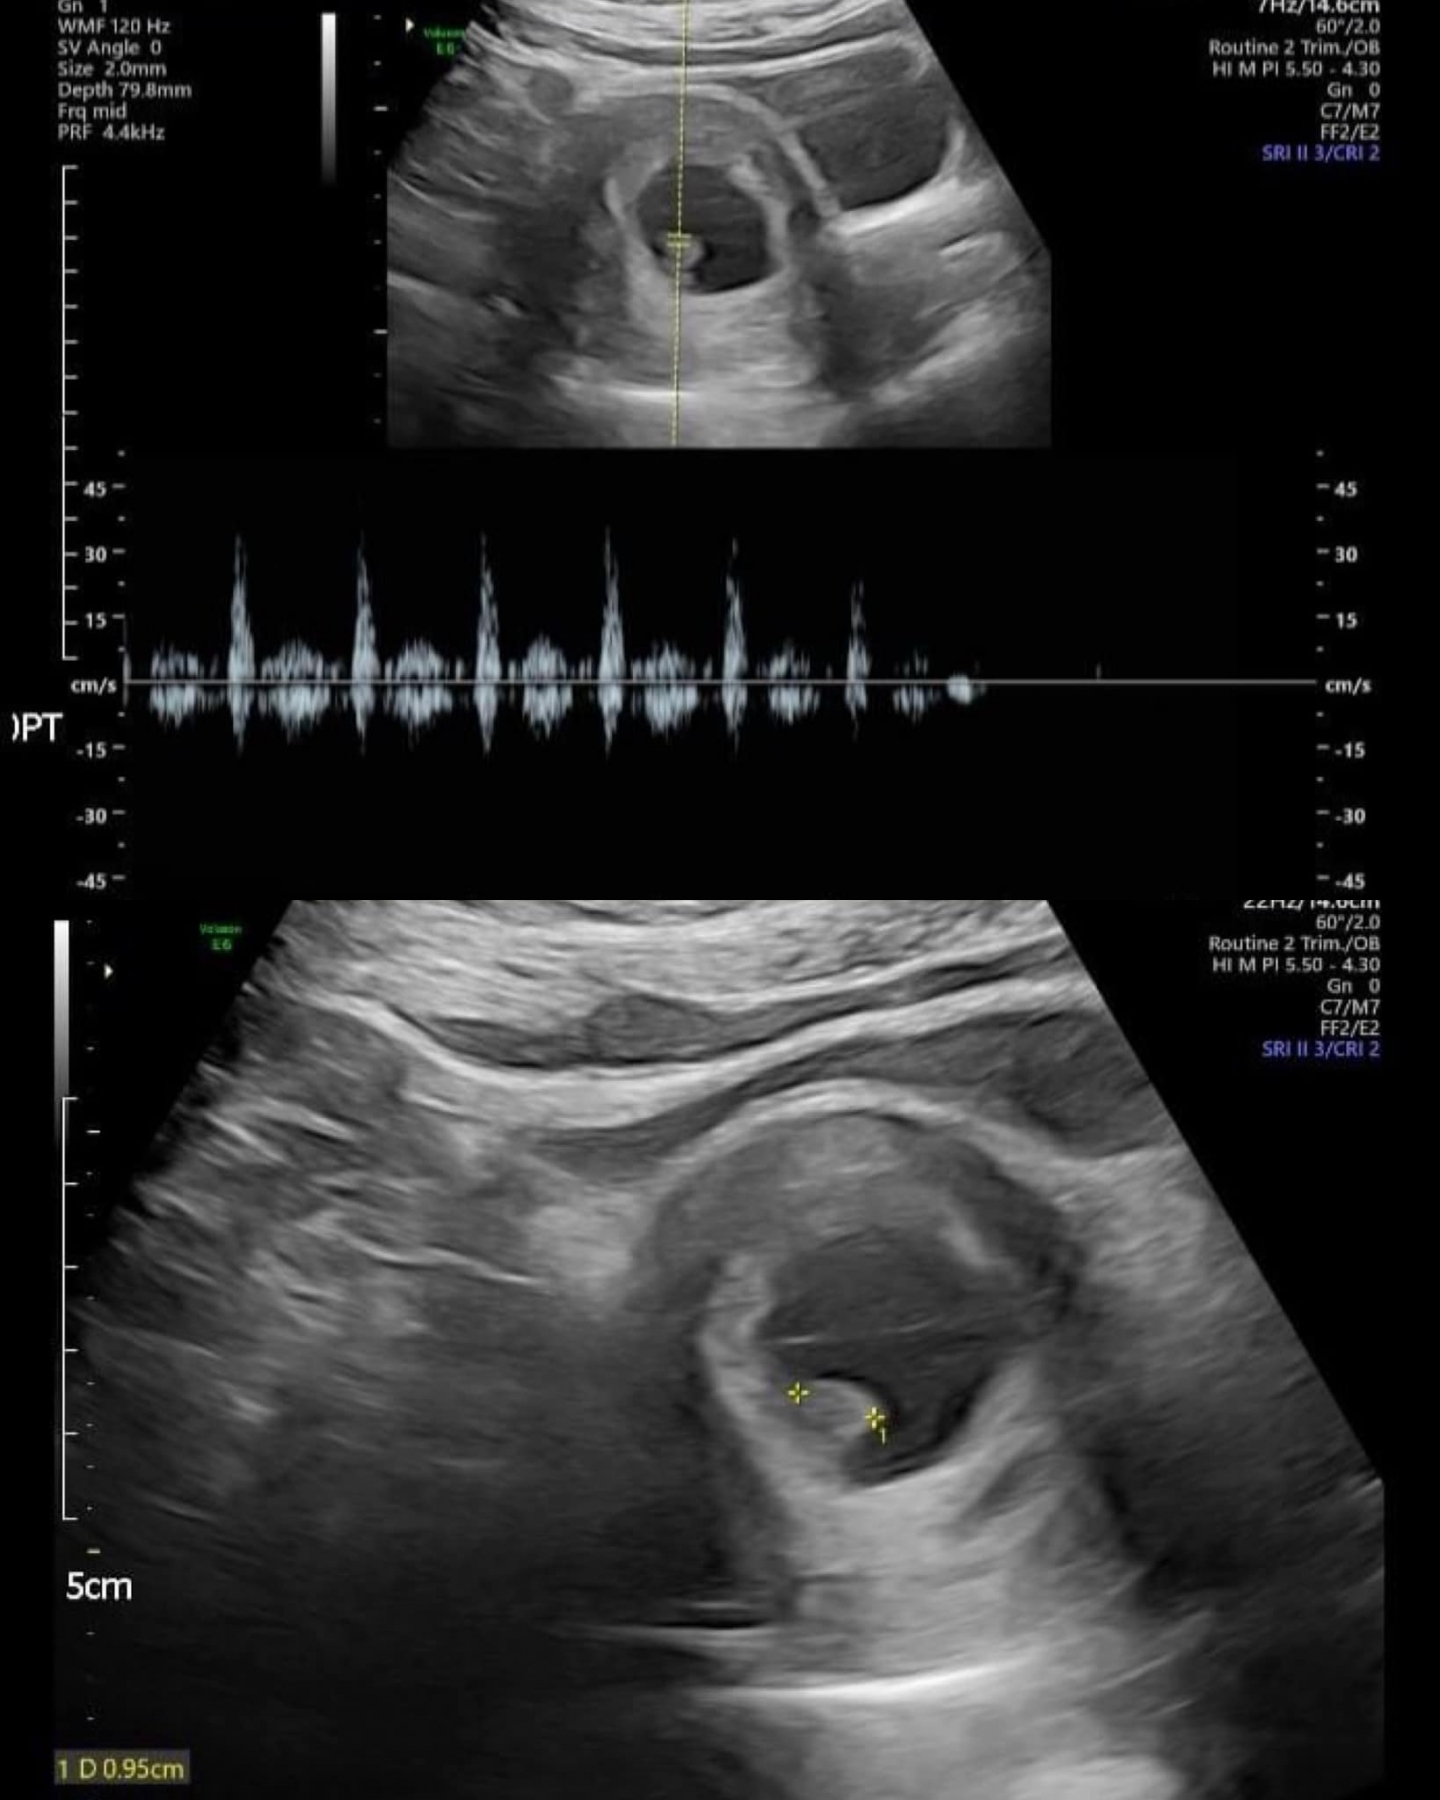

取卵那一天,成功取出了21顆卵子,但胚胎發育並不理想,因此建議在第三天的時候冷凍6顆胚胎。

數月之後,三顆精心挑選的第三天胚胎被小心翼翼地移植進她的子宮。

兩周後的驗孕日,手裡捧著的驗孕報告終於顯示出了兩條線,還記得那天夫妻倆在診間哭到不能自己(差點我也跟著掉淚)

接下來的每一次產檢,都是他們最緊張的時刻。從最初的兩個胚胎,最終保留了一個健康的胎兒,雖然有些遺憾,但更多的是慶幸和感恩。

當胎兒的心跳聲在檢查室內回蕩時,他們的世界充滿了希望和喜悅。 她順利地迎來了她們的寶寶。